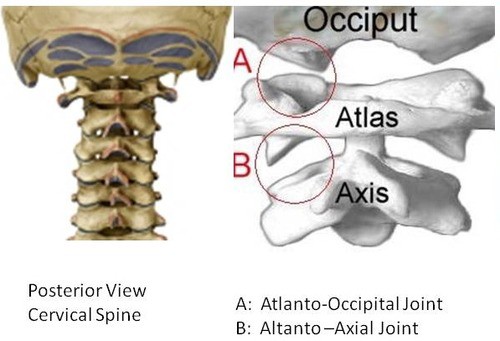

Obr. 2: Antlatookcipitální skloubení (zdroj: https://quizlet.com/29042306/joints-flash-cards/)

Krční páteř je velmi namáhanou oblastí vzhledem k její velké mobilitě oproti ostatním úsekům páteře. V souvislosti s bolestmi hlavy se jedná zejména o horní úsek krční páteře, první dva krční obratle, na které nasedá těžká lebka. Právě v úseku nazvaném antlantooccipitální skloubení (AO skloubení), spojení atlasu (první krční obratel) a lebky (záhlaví latinsky occiput), dochází k častým blokádám nejčastěji při dlouhodobé nevhodné poloze hlavy, kdy je hlava v předsunutém držení zároveň s mírným záklonem záhlaví. Blokády můžeme nalézat i v nižších úsecích krční páteře až po CTh přechod, ale ne vždy je v tomto úseku přítomný zjevný blok.